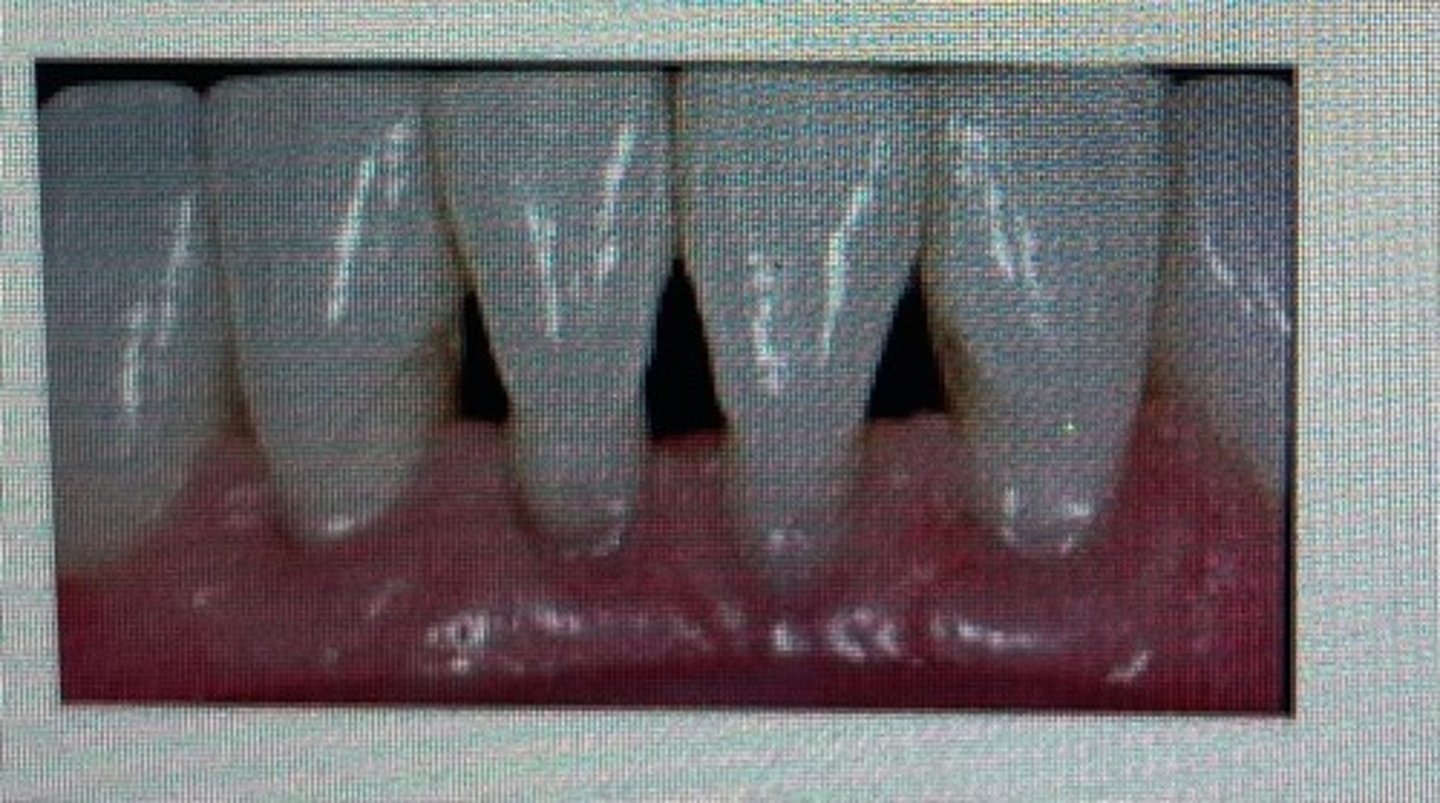

pointed papilla

blunted papilla

bulbous papilla

cratered papilla

rolled margins